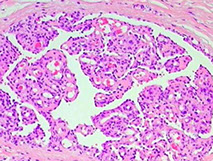

Glomeruloid Hemangioma

Rare cutaneous hemangioma assoc c POEMS syndrome (Polyneuropathy, Organomegaly, Endocrinopathy, M protein/Myeloma, Skin (hemangiomas) and Sclerotic bone lesions)

Golumeruloid hemangioma